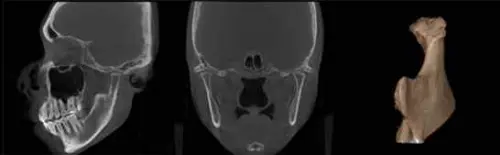

이번 연구의 주요한 분석 자료로 활용된 치과 엑스레이인 ▲파노라마(Panoramic View) ▲3차원 콘빔씨티(CBCT; Cone Beam CT), ▲두부방사선 사진(Cephalometric X-ray)의 영상 이미지들이 주요한 의학적 질환의 진단 도구로도 활용 가치가 있음이 입증됐다.

즉, 치과 엑스레이 이미지 분석을 통해 ▲악안면부에 생길 수 있는 낭 · 양성 종양 · 악성 종양 및 기타 골질환, ▲턱관절의 퇴행성골관절염, ▲림프절 석회화 등의 진단에 기여했고 의학적 치료에 연계되어 조기 치료에 도움 됨을 판단하게 된 것이다.

이외에도, 림프절 석회화, 편도 결석, 동맥 석회화 및 타석 등을 확인할 수 있었다. 석회화된 동맥이 관찰될 경우에는 뇌혈관 혹은 심혈관 질환의 문제를 확인하기 위해 꼭 내과의의 진료가 필요한 상황이다.